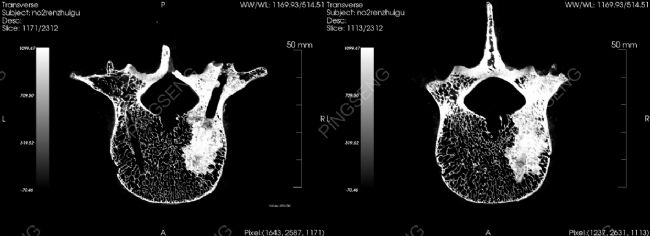

在骨水泥的研究中,我們可以選擇比人體CT具備更高分辨率和使用靈活度的顯微CT,即Micro CT來進行。接下來,小編帶來一個使用Micro CT 設(shè)備的離體人椎骨的案例。該實驗使用了我司Micro CT(型號:NEMO)掃描,并通過我司的影像軟件Avatar處理后,可以觀察到椎體內(nèi)部的缺損結(jié)構(gòu)以及骨水泥注入后的形態(tài),計算彌散體積等。

知識點:骨水泥是骨粘固劑的常用名,是一種用于骨科手術(shù)的醫(yī)用材料,由于它的部分物理性質(zhì)以及凝固后外觀和性狀頗像建筑、裝修用的白水泥,便有了如此通俗的名稱。骨水泥注入椎體內(nèi)沿骨折線及骨小梁間隙彌散,粘合骨小梁及其包繞的空間,形成一種由骨小梁、骨水泥,骨小梁間隙的三維空間結(jié)構(gòu),該空間即為骨水泥在椎體骨的彌散體積。

注入某骨水泥后人椎骨不同橫截面展示